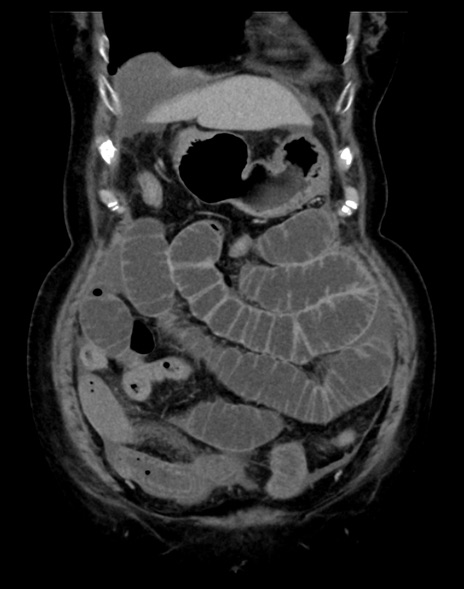

症例13 CT(冠状断像)1日半後